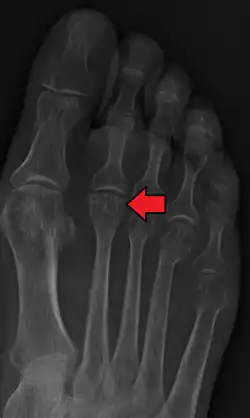

| Freiberg disease as seen on plain film | |

- Radiography: X-rays may reveal flattening, sclerosis, or fragmentation of the metatarsal head.